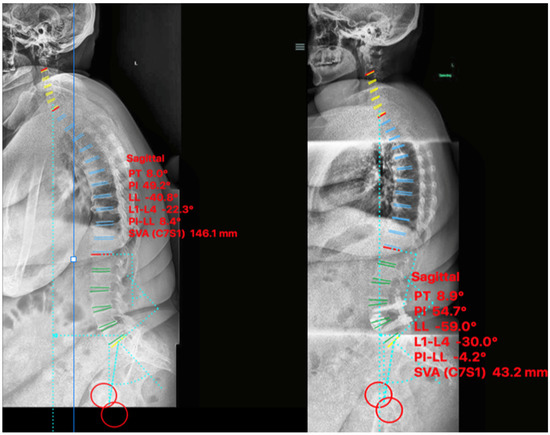

2.4.1. Case I

2.4.2. Case II

2.4.3. Case III